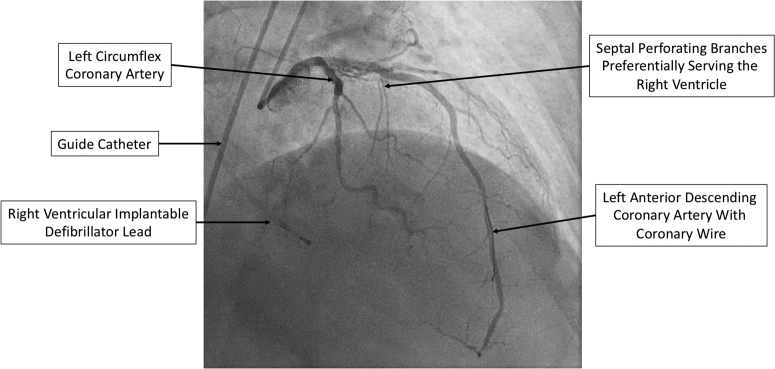

Figure 2.

Right Anterior Oblique Coronary Angiogram

Right anterior oblique coronary angiogram demonstrating significant right ventricular involvement of the first 2 septal perforating branches of the left anterior descending coronary artery.

Coronary angiography revealed that the first 2 septal perforating branches of the left anterior descending had significant right ventricular involvement, and did not supply the hypertrophied basal septum (Figure 2). For this reason, ASA was aborted. The patient was then referred for endocardial radiofrequency ablation of septal hypertrophy (ERASH) guided by intracardiac echocardiography (ICE) and electroanatomic mapping.